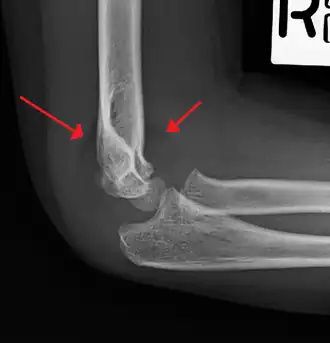

On lateral view of the elbow, there are five radiological features should be looked for: tear drop sign, anterior humeral line, coronoid line, fish-tail sign, and fat pad sign/sail sign (anterior and posterior).[3][8]

Tear drop sign - Tear drop sign is seen on a normal radiograph, but is disturbed in supracondylar fracture.[8]

Anterior humeral line - It is a line drawn down along the front of the humerus on the lateral view and it should pass through the middle third of the capitulum of the humerus.[9] If it passes through the anterior third of the capitulum, it indicates the posterior displacement of distal fragment.[8]

Fat pad sign/sail sign - A non-displaced fracture can be difficult to identify and a fracture line may not be visible on the X-rays. However, the presence of a joint effusion is helpful in identifying a non-displaced fracture. Bleeding from the fracture expands the joint capsule and is visualized on the lateral view as a darker area anteriorly and posteriorly, and is known as the sail sign.[8]

Coronoid line - A line drawn along the anterior border of the coronoid process of the ulna should touch the anterior part of the lateral condyle of the humerus. If lateral condyle appears posterior to this line, it indicates the posterior displacement of lateral condyle.[8]

Fish-tail sign - The distal fragment is rotated away from the proximal fragment, thus the sharp ends of the proximal fragment looks like a shape of a fish-tail.[8]